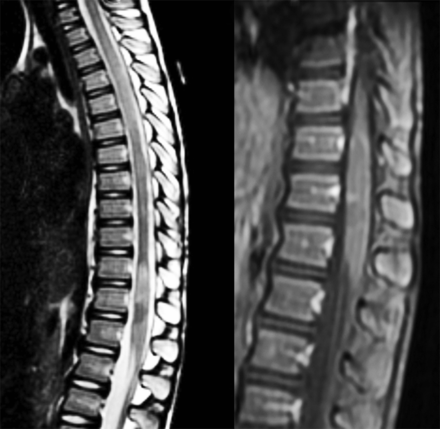

图2

图2 复发性纵广泛的横向脊髓炎患者MOG抗体

矢状t2加权MRI脊髓的一个6岁的女孩与复发性纵广泛的横向脊髓炎和髓少突细胞糖蛋白(MOG)抗体(效价1:1,024)显示2纵向广泛的病变。在t1矢状序列,在胸腰椎损伤过渡环对比度增强。